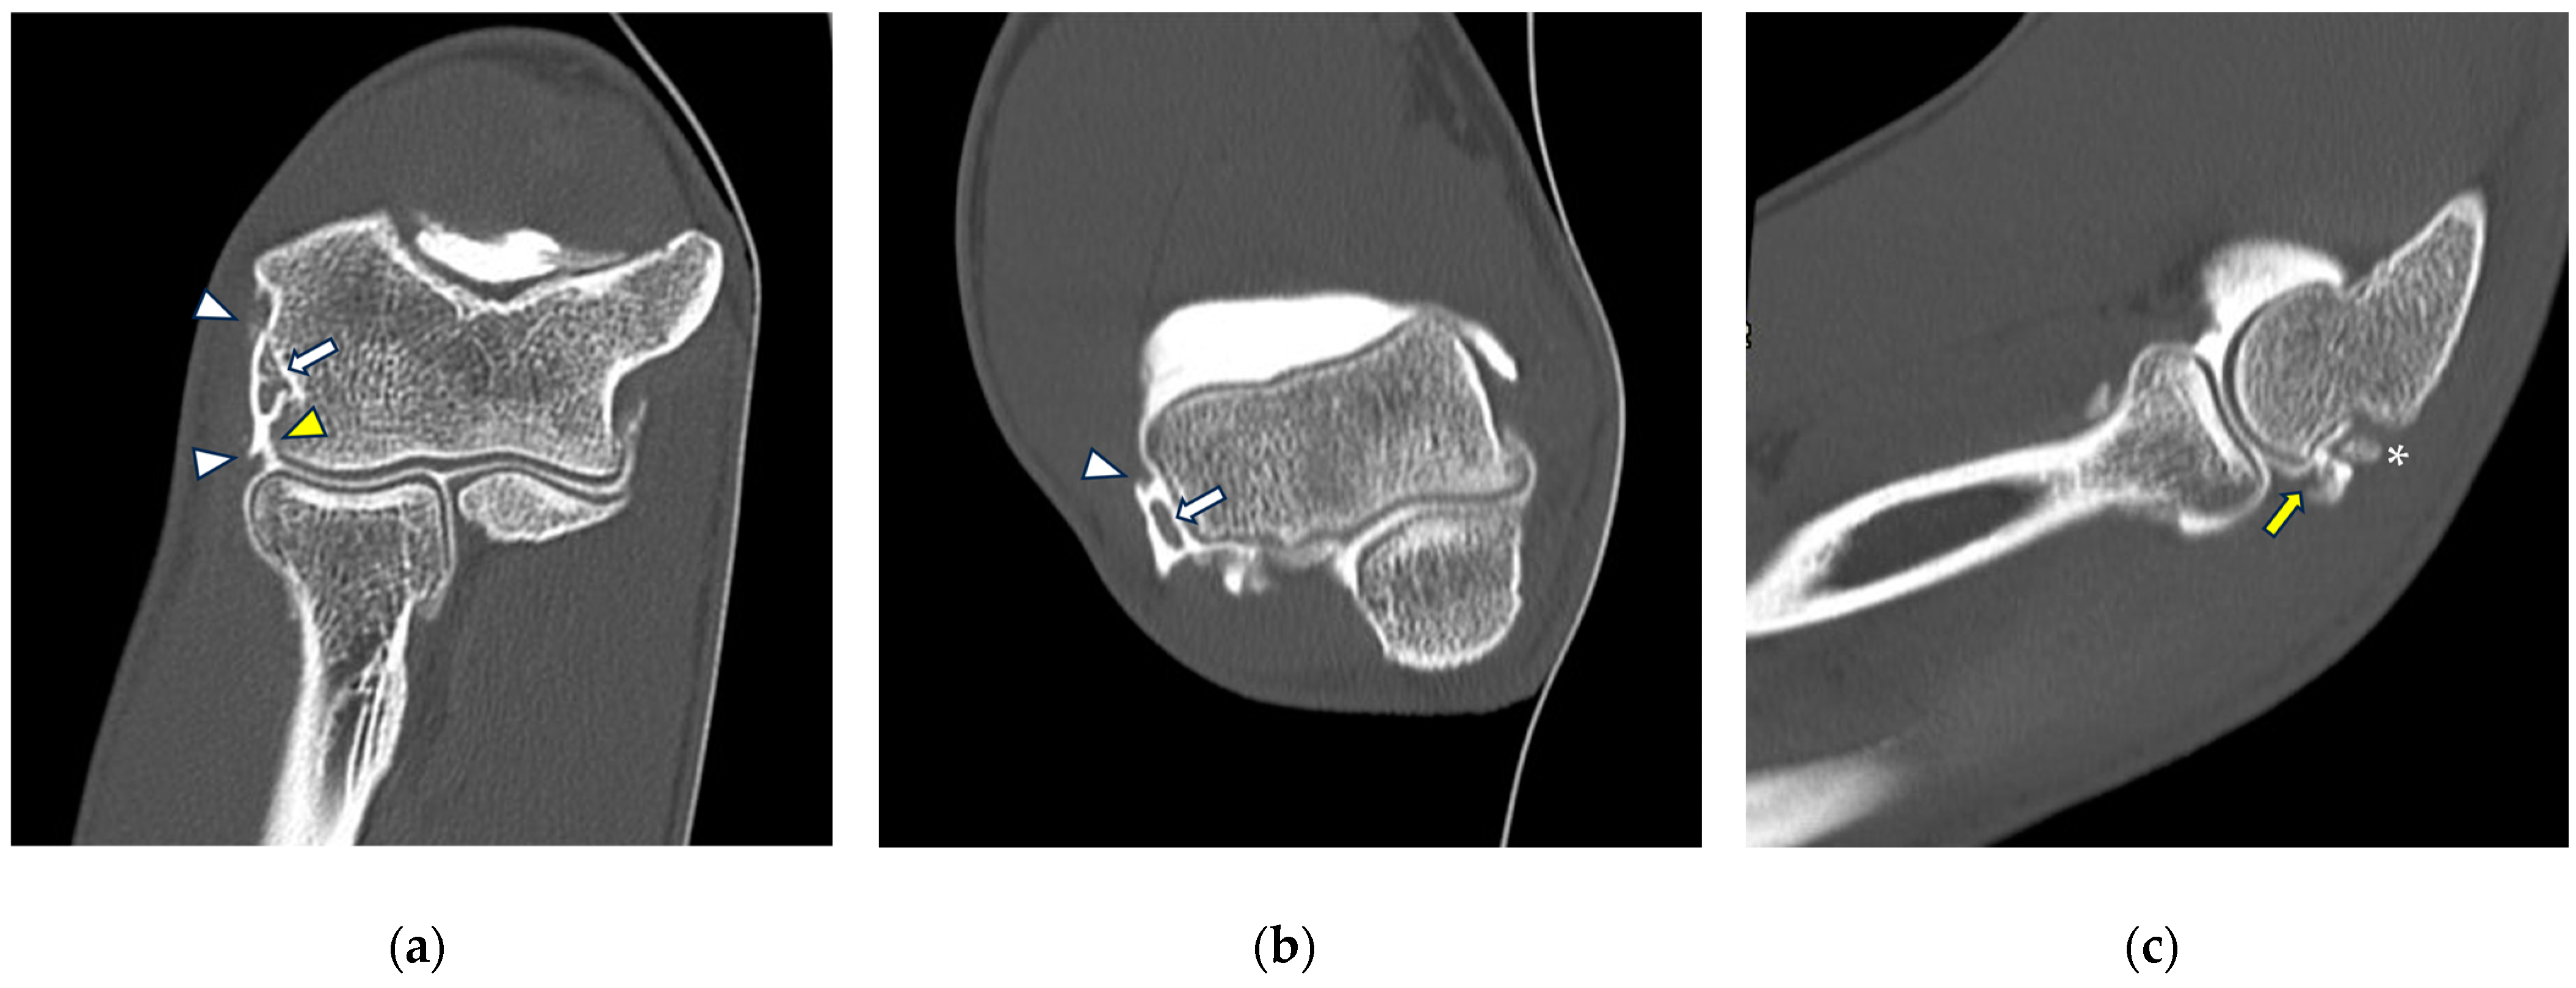

Figure 6.

CT-arthrography of a professional motocross rider with chronic elbow pain due to repeated microtraumatism. (a,b) Axial and sagittal images show pathological widening of the postero-lateral recess (yellow arrows); (b,c) sagittal and coronal images show articular asymmetry of the humero-radial joint (asterisks), diffuse cartilage fraying and a full-thickness chondral defect (grade IV) of the posterior aspect of the radial head dish (yellow arrowhead).